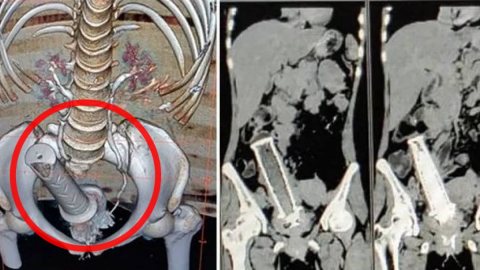

เจ็บทรมานน่าดู!! ภรรยาถูกสามีขู่ ไม่ให้บอกใคร หลังสามีใช้ แฮนด์มอไซค์ สอดช่องคลอด ระหว่างเมา